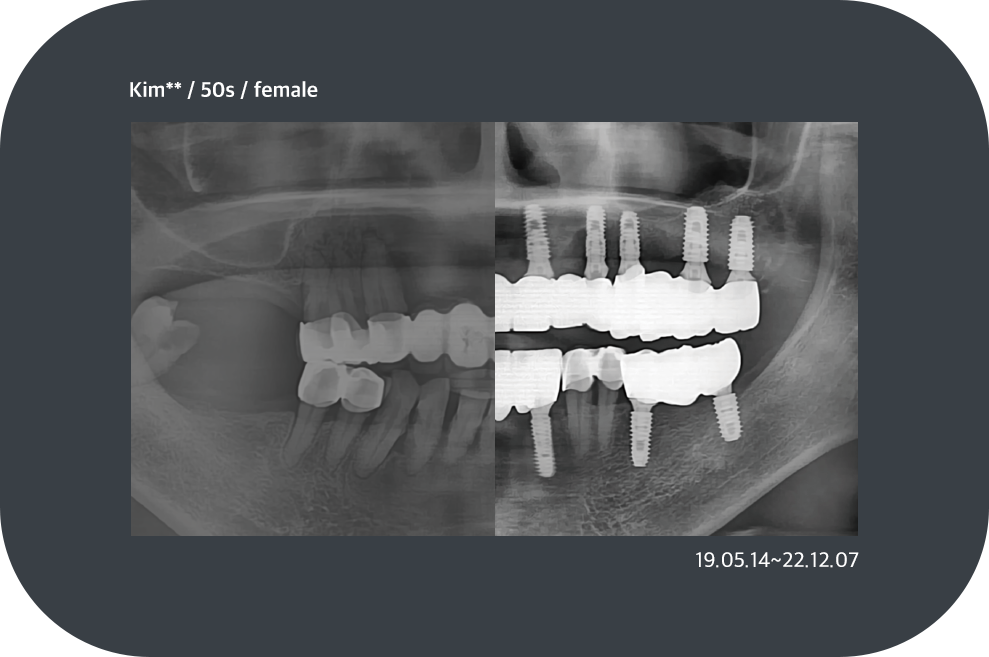

치료사례

임플란트 치료사례

implant_case01

implant_case02

implant_case03

implant_case04

implant_case05

implant_case06

implant_case07

implant_case08

implant_case09

implant_case10

implant_case11

implant_case13

implant_case14

*모든 증례 사진은 의료법 제23조, 제56조에 의거하여, 당사자의 동의하에 게시하였습니다.

*치료 사진은 모두 본원에서 치료한 환자분의 사진입니다.

*치료 사진은 모두 동일인의 사진이며, 동일조건에서 촬영하였습니다.

*개인의 차이에 따라 시술 및 수술 후 부작용이 발생할 수 있으며, 의료진과 충분한 상담을 받으시기 바랍니다.